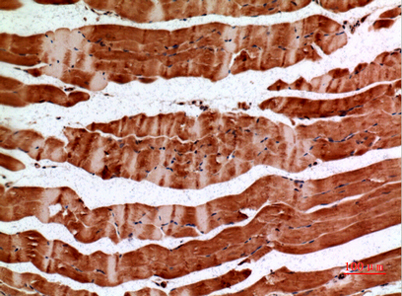

Product name: ALDH2 rabbit pAb

Dilutions: Western Blot: 1/500 - 1/2000. IHC-p: 1/100-1/300. ELISA: 1/20000. Not yet tested in other applications.

Immunogen: The antiserum was produced against synthesized peptide derived from the N-terminal region of human ALDH2. AA range:41-90